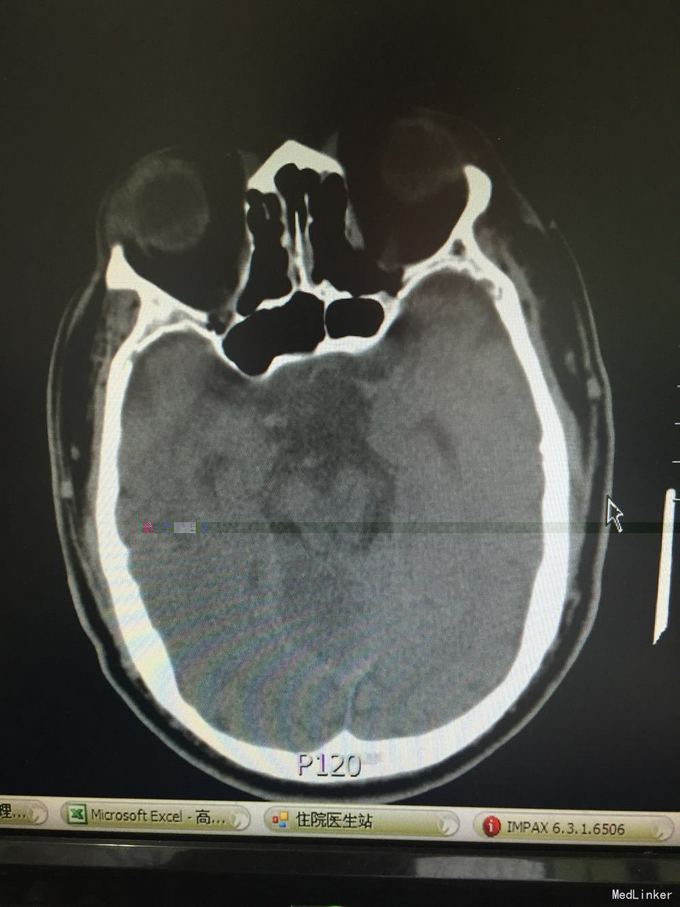

患者因突发意识不清3小时入院。既往脑梗死、高血压、糖尿病史,控制不佳。该患者于入院前3小时无明显诱因在工作中突发意识不清,起病时呼唤能回答,但口齿不清,伴右侧肢体无力,不能持物及行走,伴头痛,呕吐,呕吐物为胃内容物,测血压大于200mmHg,意识障碍快速进展加重,成昏睡状态,由120到我院,查头CT示:多发脑梗死。

T:36.0 脉搏 96 呼吸18 血压200/100,浅昏迷,双侧瞳孔等大同圆,对光反射存在,双眼右侧凝视,双眼球浮动,鼻唇沟对称,疼痛刺激后左侧肢体可正常活动,右侧肢体活动差,右侧肌张力减低,腱反射对称,右下肢病理征(+),